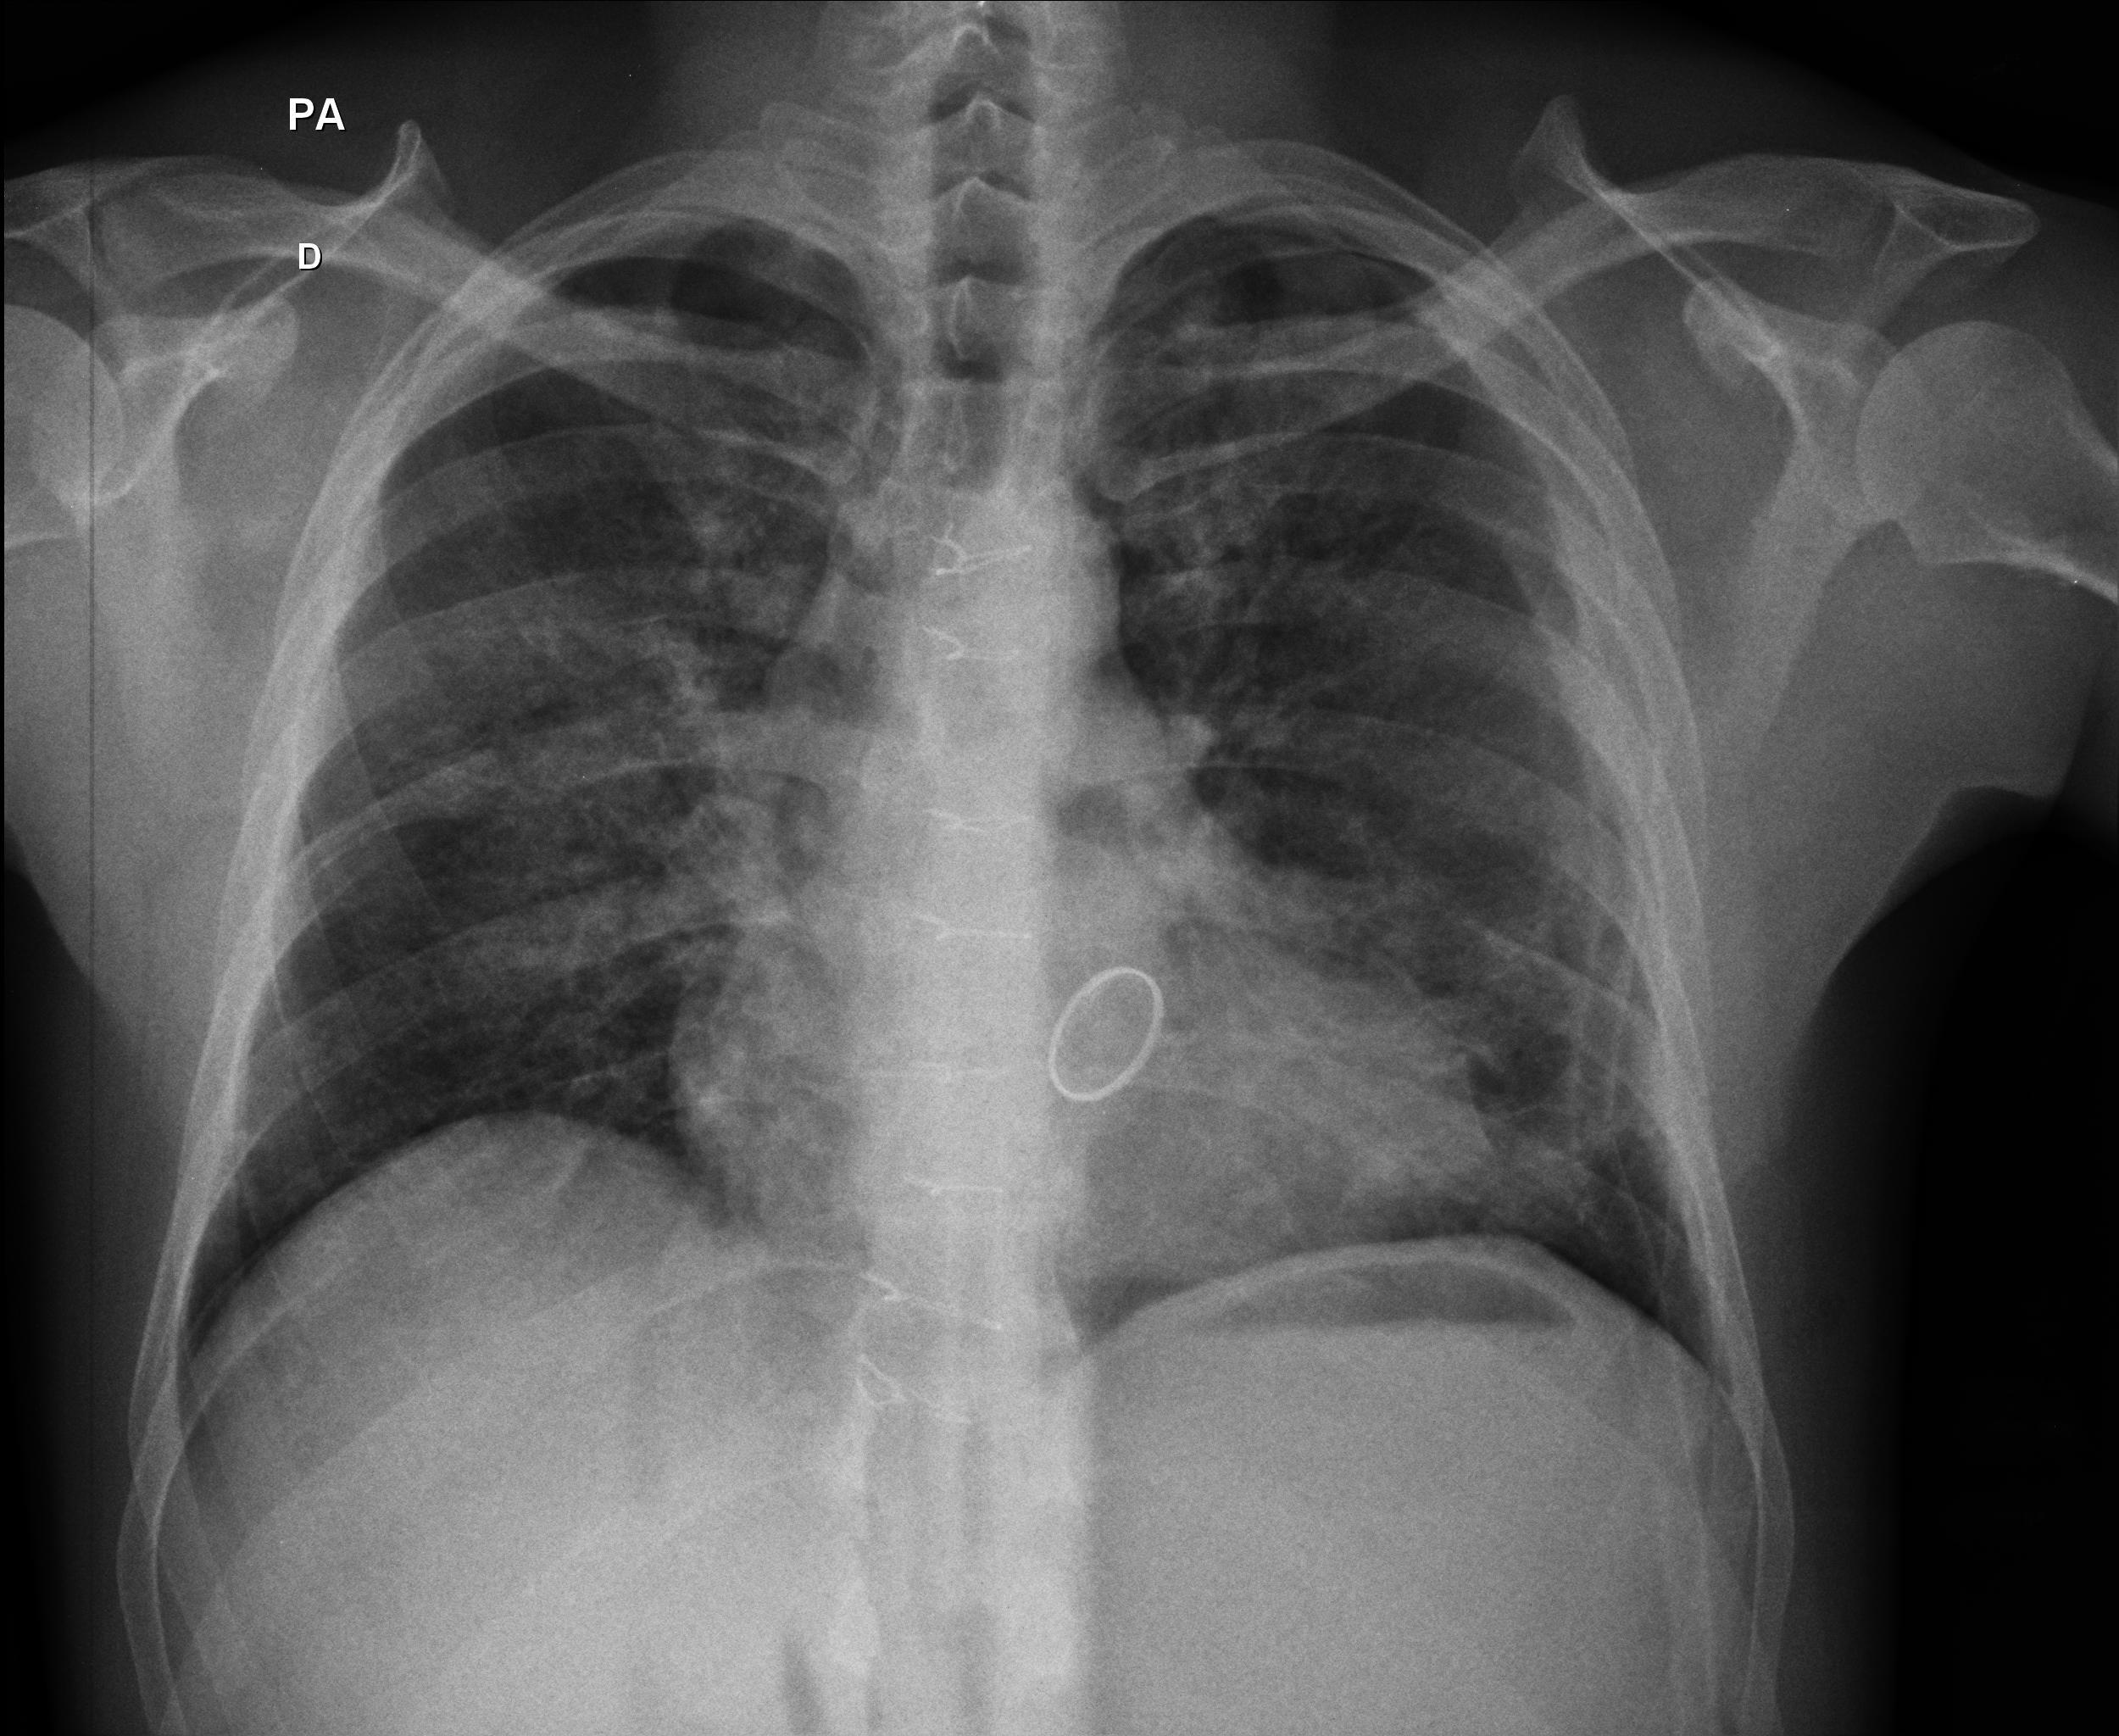

Caso Número 4/2018: “Uma sessão interativa de casos em radiologia torácica – Parte 1”

Caso relatado na Reunião de Discussão de Casos Clínicos do Hospital Universitário Prof. Polydoro Ernani de São Thiago, iniciada pelos Profs. Jorge Dias de Matos, Marisa Helena César Coral e Rosemeri Maurici da Silva, em julho de 2017. No dia 14 de junho de 2018, no auditório do HUPEST, realizou-se a apresentação e discussão do caso cujo registro é apresentado a seguir. Trata-se da discussão de onze casos em radiologia torácia, de forma interativa com a plateia, e assim ocorre também neste artigo.